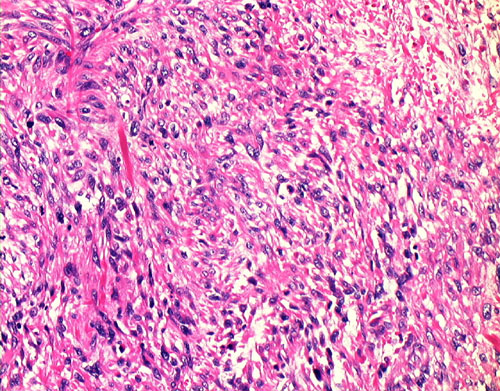

19. Fibrosarcoma

19-4.JPG (127110 bytes)19-10.JPG (125959 bytes)19-20.JPG (136926 bytes)19-40.JPG (112275 bytes)